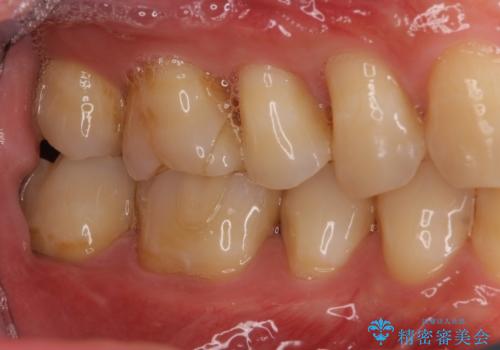

- 他院で行った、古いセラミックが欠けたとのことでご来院された患者様です。

古いセラミックを外すと、無数のヒビが入っており、そこからできた新しい虫歯がありました。

古い材料も虫歯もすべて除去して、根本からやりかえました。

セラミックが欠けるほど強い力がかかっているということは、ご自身の歯も割れている(小さいヒビ等も含む)可能性があります。拡大鏡でしっかり見ながら治療します。